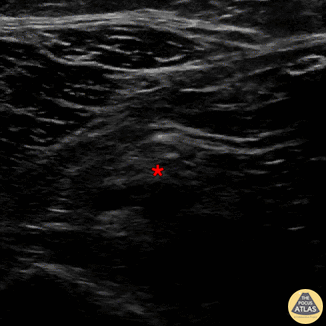

In-plane common peroneal nerve block, with needle entering from the medial aspect. Sequential injection of anesthetic, eventually injecting superficial to common peroneal nerve (*). The proximal fibula cortex is visible at bottom of screen left. Denver Health Ultrasound Fellowship Archive